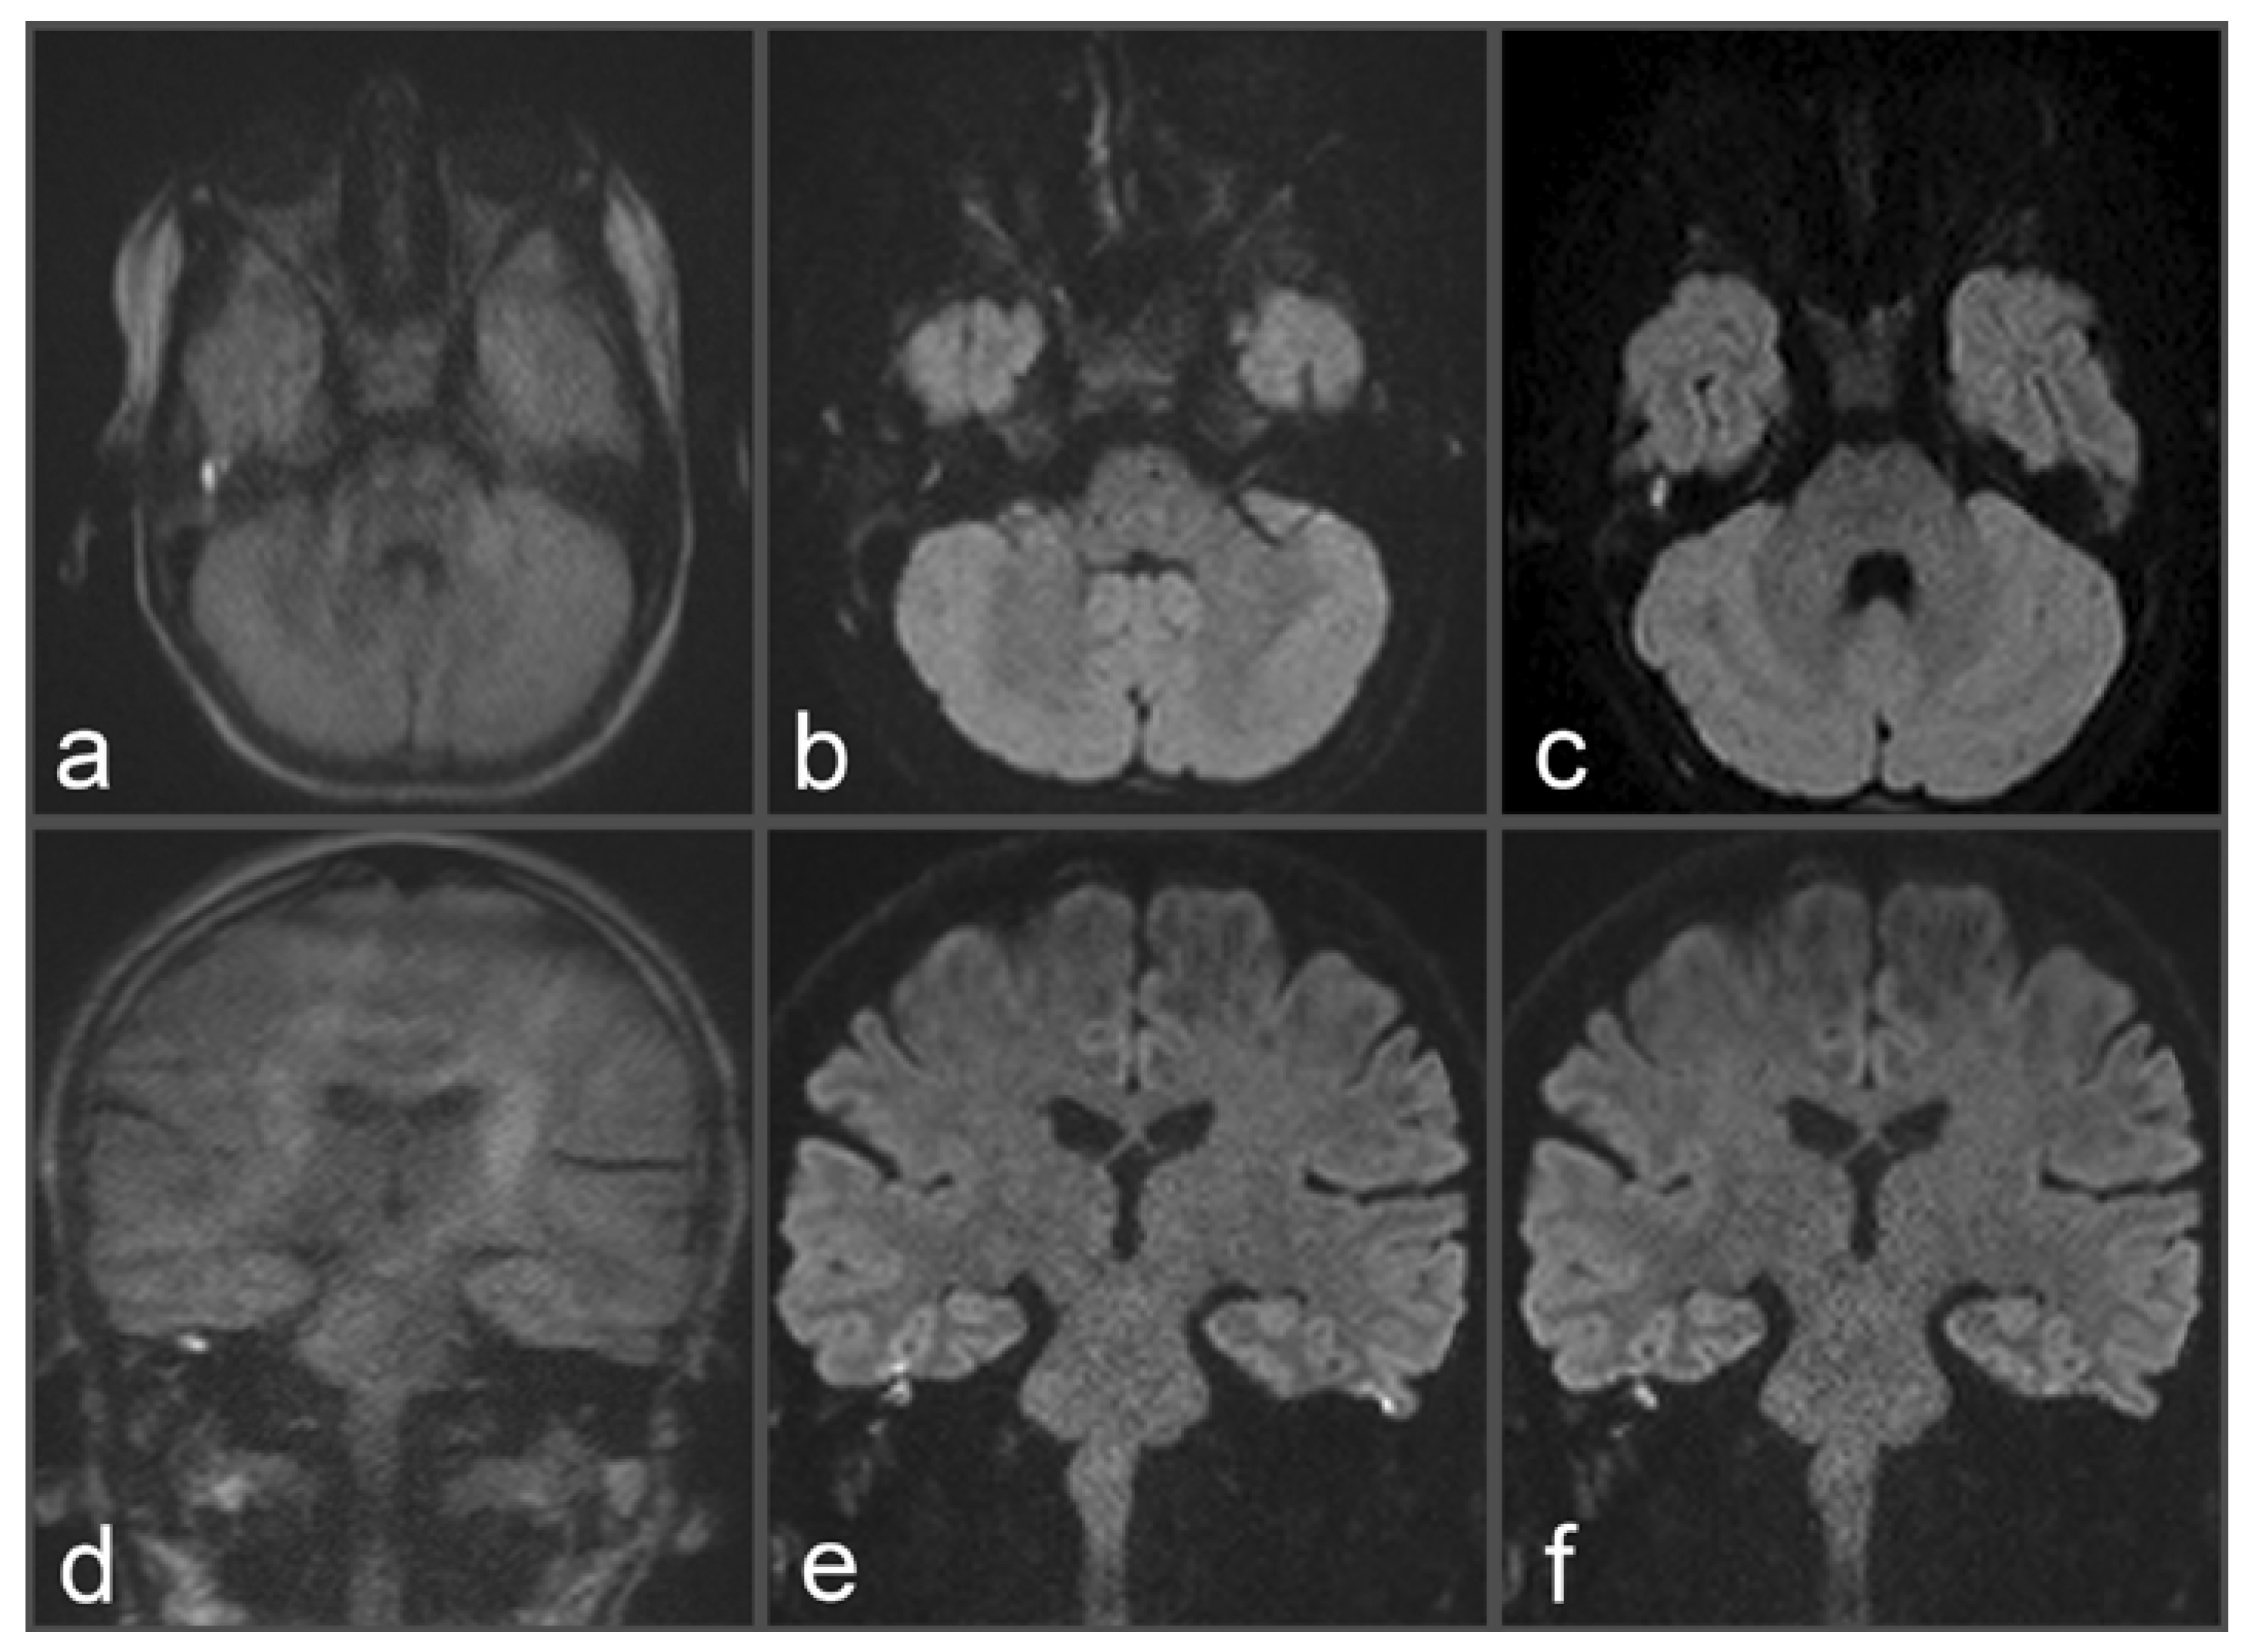

Figure 1. Images of a 34-year-old patient with a suspected cholesteatoma on the right side. (a) and (c) uncorrected rsDWI (coronal and axial slice orientation). (b) and (d) topup-corrected rsDWI (coronal and axial slice orientation). Field inhomogeneities at the height of the upper temporal bone generate a brightly appearing lesion in the uncorrected rsDWI images which might be mistaken for a cholesteatoma lesion. Notably, the lesion shows a geometrical distortion on axial slice orientation, whereas a rounded appearance could be identified on coronal image. After topup-correction, the brightly appearing lesion on the right side disappeared completely, unmasking the lesion as an artifact. The “no cholesteatoma” diagnosis was confirmed after surgery with negative histopathological proof.